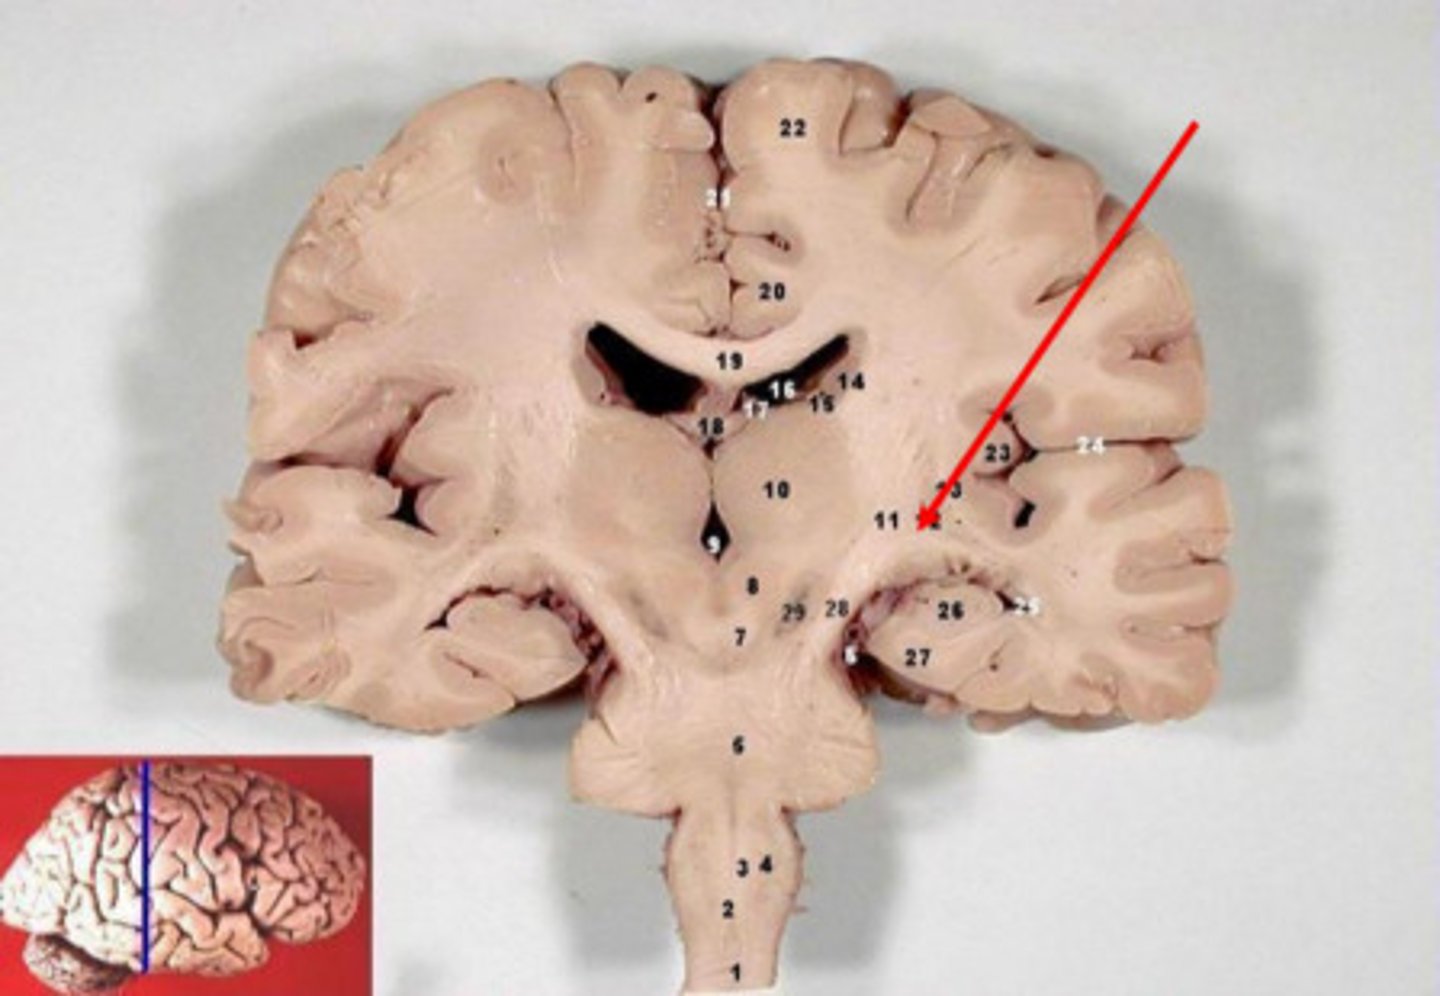

gyrus (pl. gyri)

Large folds of tissue covering the surface of the cerebrum

sulcus (pl. sulci)

shallow grooves separating the gyri

cerebrum

longitudinal fissure

deep cleft that separates cerebral hemispheres

lobes of the cerebrum

frontal, parietal, temporal, occipital, insula

frontal lobe

parietal lobe

occipital lobe

temporal lobe

insula

central sulcus

separates frontal and parietal lobes

lateral sulcus

Separates temporal lobe from parietal and frontal lobes

cingulate gyrus

plays role in expressing emotions via gestures and resolves mental conflict

corpus callosum

A thick band of axons that connects the two cerebral hemispheres and acts as a communication link between them.

Diencephalon

central part of the brain made up of the thalamus, hypothalamus, and epithalamus

thalamus

hypothalamus

brainstem

cerebellum

gray matter

Brain and spinal cord tissue that appears gray with the naked eye; consists mainly of neuronal cell bodies (nuclei) and unmyelinated axons.

white matter

Whitish nervous tissue of the CNS consisting of myelinated axon